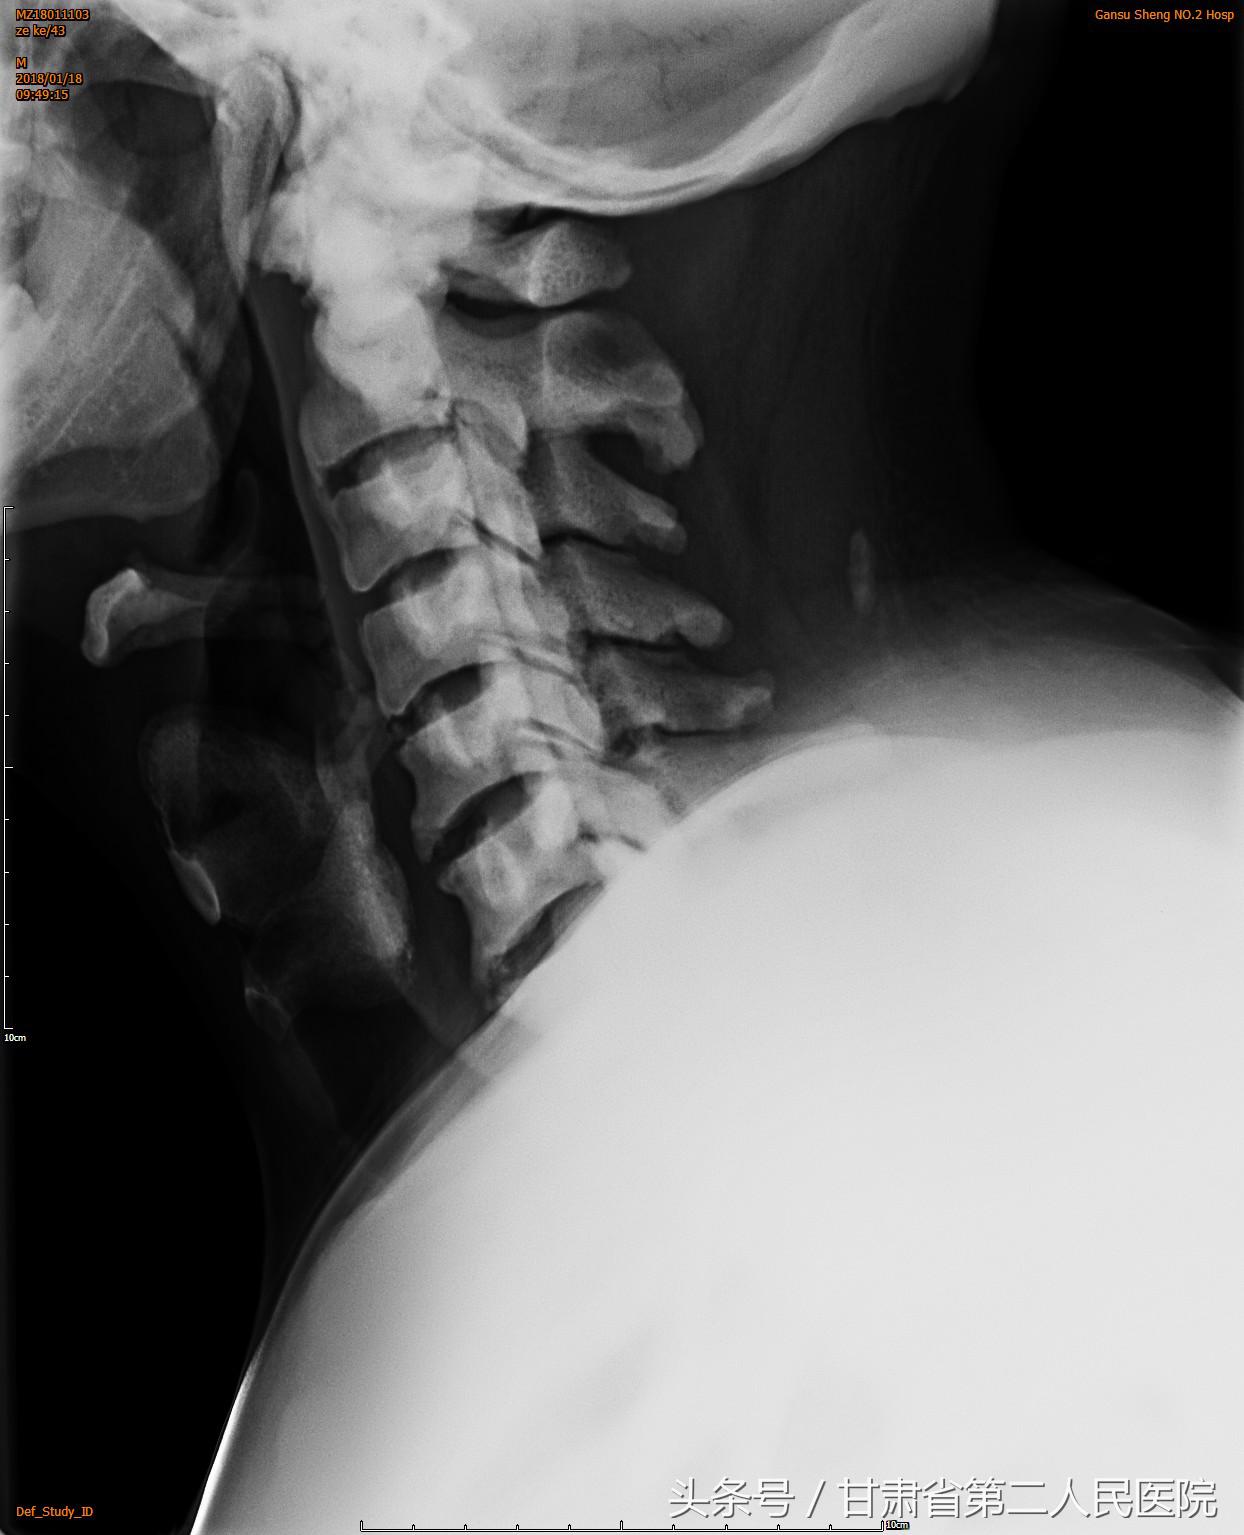

入院后行全脊柱X线、CT及MRI示:C3-6颈椎后纵韧带骨化引起的脊髓型颈椎病,并有严重的石骨症。

可见后纵韧带骨化